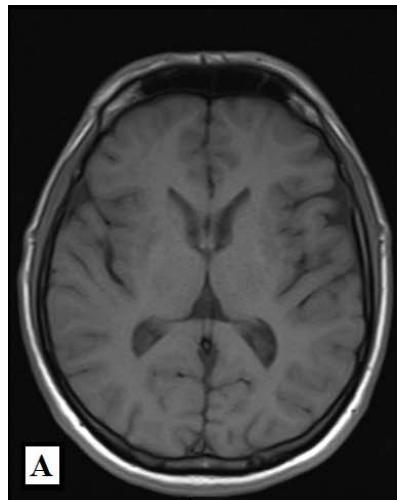

We report a rare case of Wilson’s Disease with neurologic features in a 31-year-old man. This disease consists of a disturbance of copper metabolism secondary to a mutation in the gene responsible for encoding the tissue transporter and the enzyme that incorporates the excess element into bile, generating toxic accumulation in the liver, cornea, and central nervous system. According to his wife, the patient had been treated for an unspecified mood disorder. The clinical picture was characterized by depressive mood, anhedonia, and anxiety. He had his first seizure episode on December 3rd, 2021. He progressed with dysarthria, ataxic gait, dystonia of the right-hand flexor muscles, and intermittent urinary incontinence. Marked worsening was observed after the diagnosis of COVID-19 in February 2022. At the clinical evaluation on March 24th, risorius muscle dystonia (risus sardonicus), resting tremor, and Kayser Fleischer rings at slit-lamp examination was also noted.

Detailed image from a research journal sample.